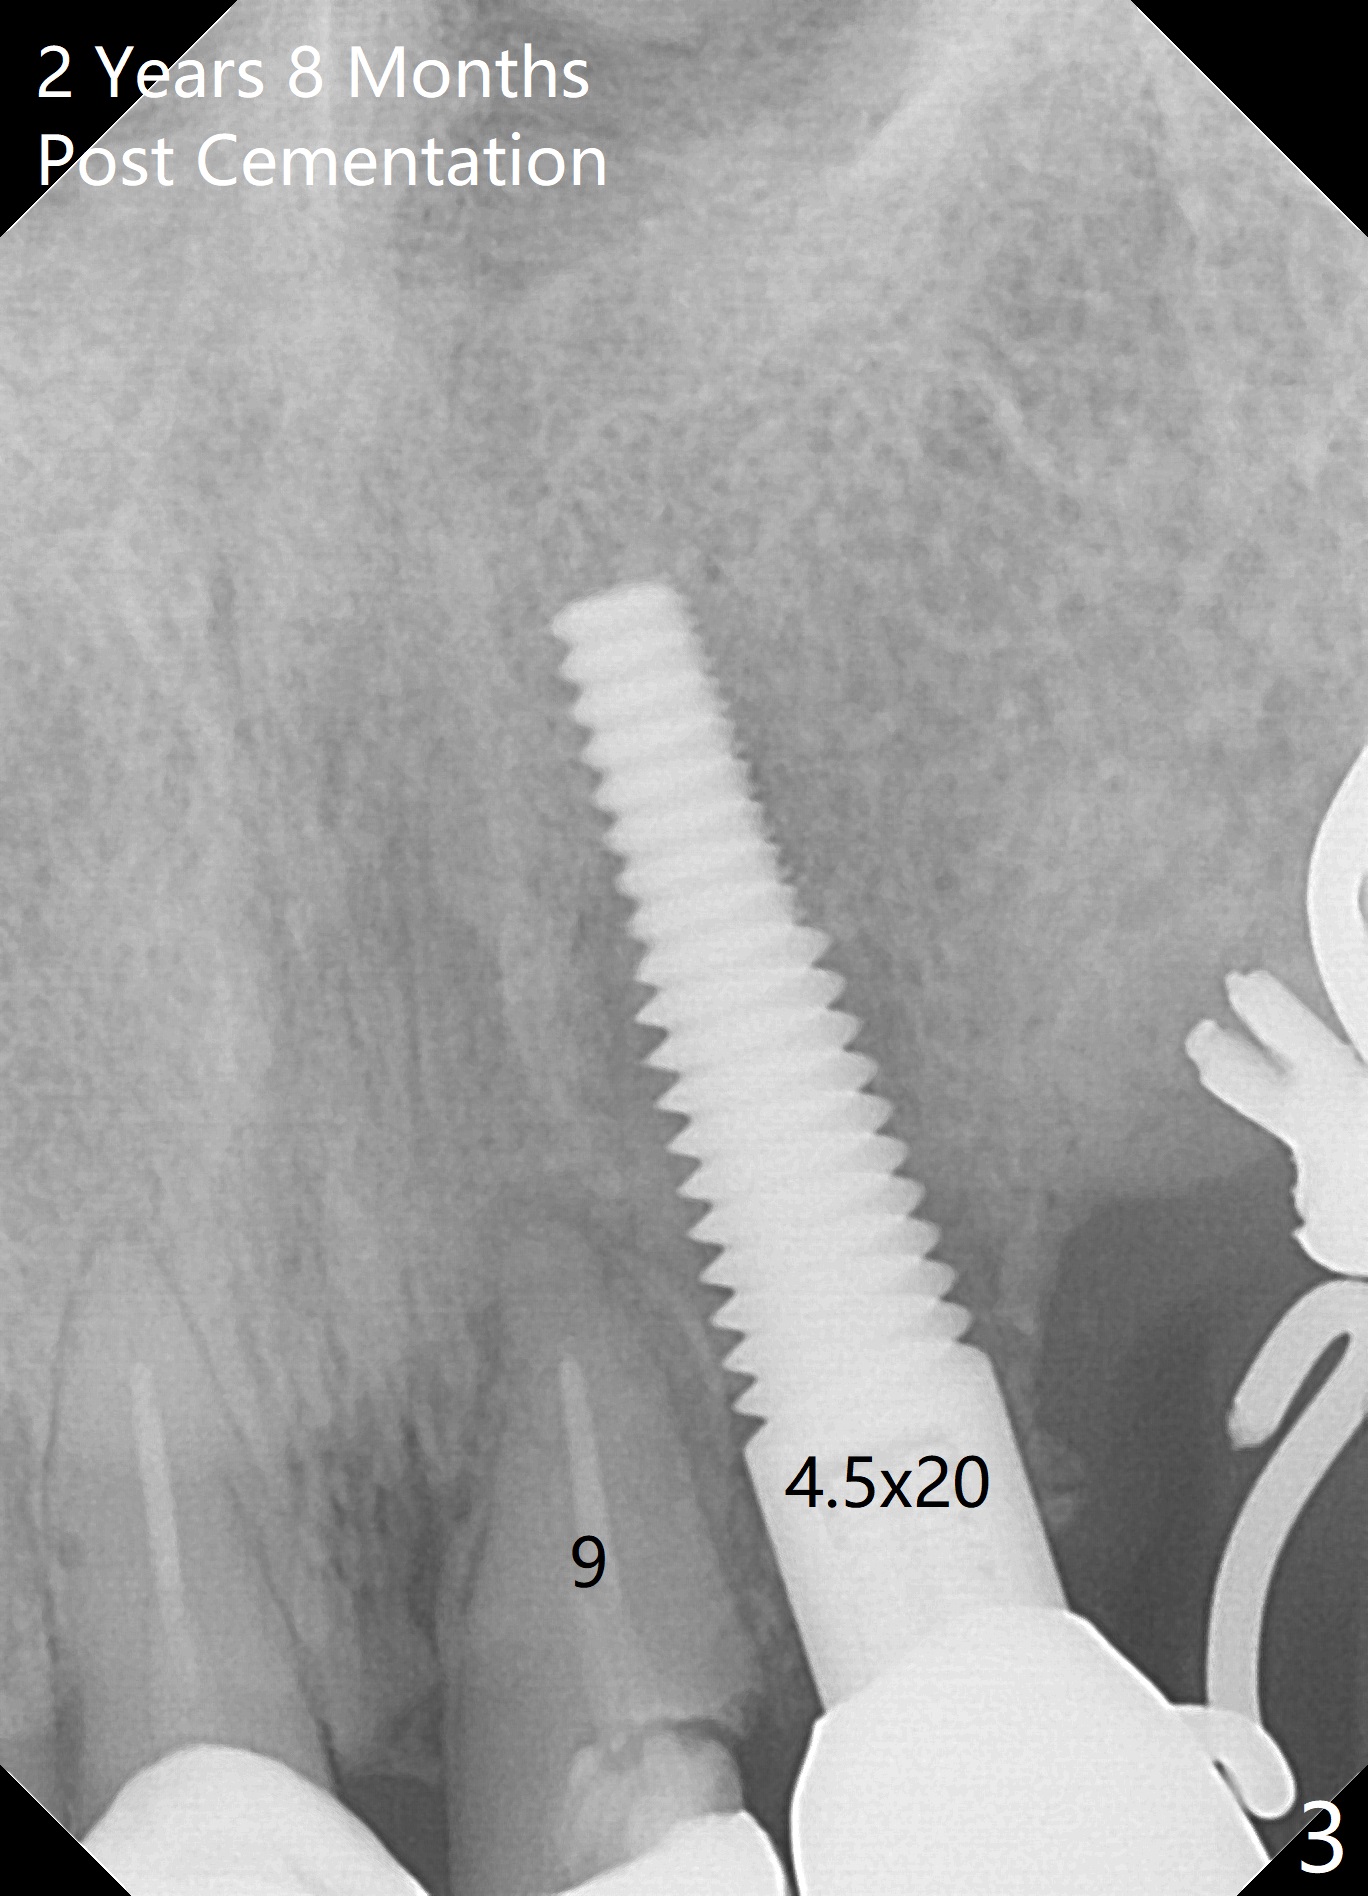

A 87-year-old woman requests implants following dislodgement of #6 and 7 crowns (Fig.1). In fact the crown at #6 is recemented. An implant will be placed at #7. To reduce the chance of buccal or palatal plate perforation, a 2.5x14 mm 1-piece implant will be used (Fig.2), in spite of a 4.5x20 mm tissue-level implant having been placed on the contralateral side (Fig.3). If the bone density at #7 turns out to be low, underprepare or use a larger implant. Prepare for socket shield.